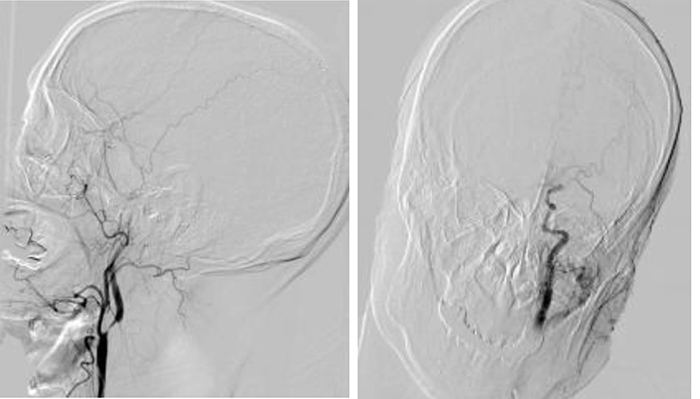

▲患者脑血管造影提示左侧颈内动脉C1段次全闭塞及左侧大脑中动脉M1段闭塞